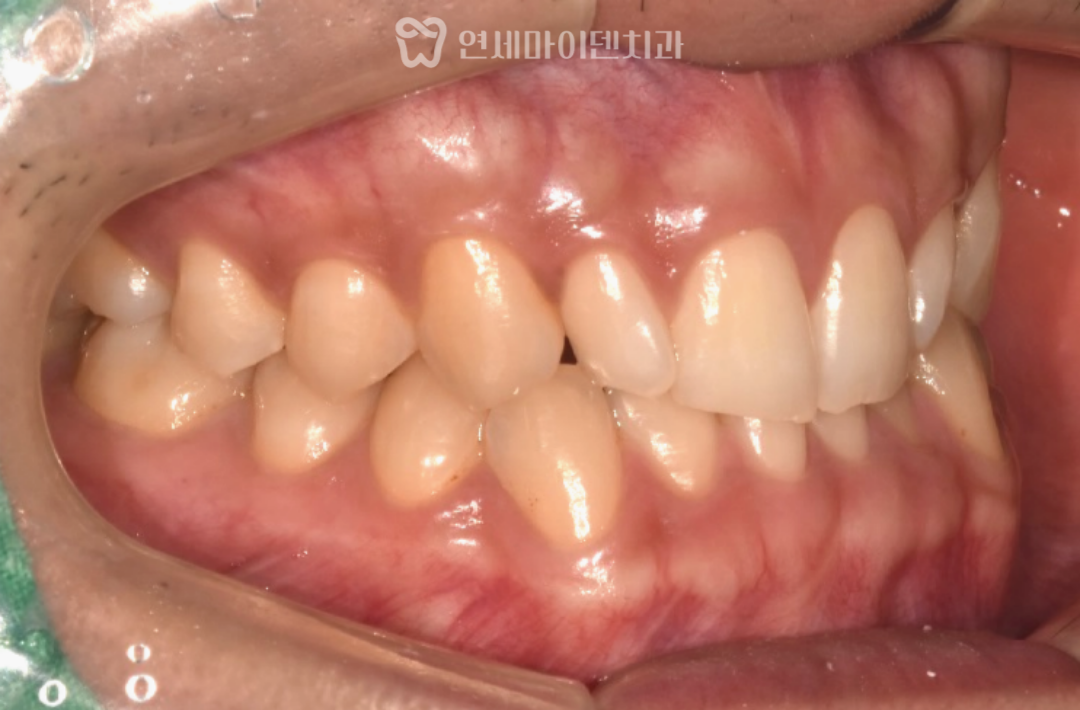

최종 치료 결과

최종적으로

위아래 치아는 가지런하게 배열되었고,

왜소치 부위는 라미네이트 보철로

심미성과 기능을 함께 보완했습니다.

치료가 진행되면서

악궁 형태는 V자에서 U자 형태로 확장되었고,

송곳니와 어금니가 세워지며

전체 배열이 점차 안정되었습니다.

입동굴 역시

과도하게 넓었던 상태에서

적절한 폭으로 줄어들며

미소가 훨씬 자연스러워졌습니다.